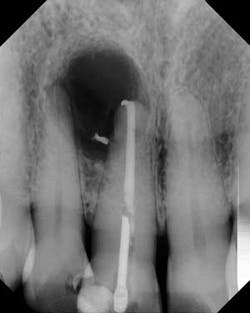

Although the literature varies as to the amount of bone volume that can be created/preserved, what material to use, as well as the indications for these procedures, (4) the majority of these studies agree that socket debridement is essential post-tooth extraction to ensure a good result. Socket debridement is particularly important when acute/chronic infections are present and cystic material lines the alveolar socket and/or tooth (figures 1 and 2). The complete removal of this infected tissue (figure 3) is tantamount to good bone fill, and can be the source of bone-graft contamination and infection.